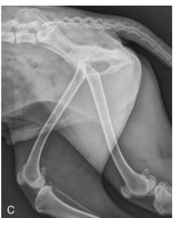

Advantage of CR and DR in regards to exposure

Perfect image quality